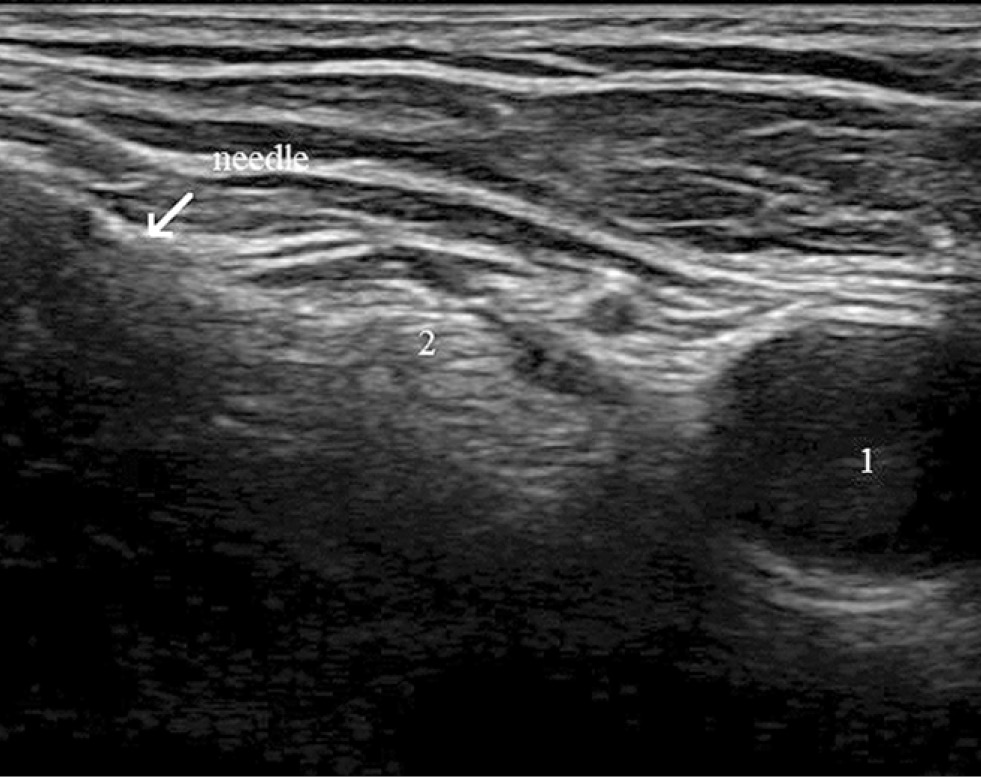

After the femoral nerve was identified laterally, an insulated block needle was inserted in-plane and advanced toward the lower portion of the femoral nerve, and 5 mL of ropivacaine 0.2% was injected (Fig. 2).

Fig. 2. Ultrasound image of the femoral nerve.

Note. 1 — femoral vein, 2 — femoral artery, 3 — femoral nerve.